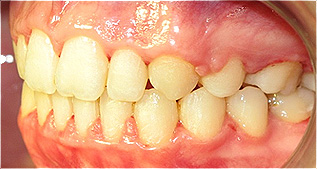

Apinhamento dentário com os dentes caninos em desoclusão (classe II, divisão 2).

![]() |